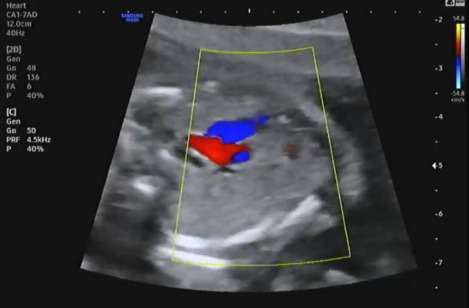

복부를 보고 장기가 주수에 맞게 잘 발달하고 있는지 확인했다. 심장, 간, 위 등 현재 잘 있는지 확인하고 심장에서 혈류가 잘 흐르고 있는지 확인했다. 심장이 심실 2, 심방 2로 잘 나뉘어 있는지 혈류가 알맞게 흐르고 있는지 확인하는데 신기했다. 혈류가 알맞게 제 방향으로 흐르는 것을 확인하고 태아의 심장이 잘 뛰고 있는지 확인했다.